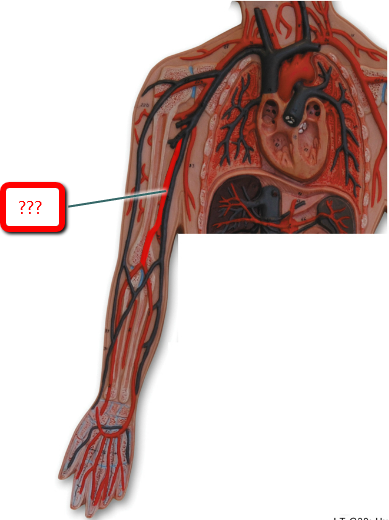

Axillary artery/vein

Brachial artery

Cephalic vein

Median cubital vein

Radial artery/vein

Subclavian artery/vein

Ulnar artery/vein